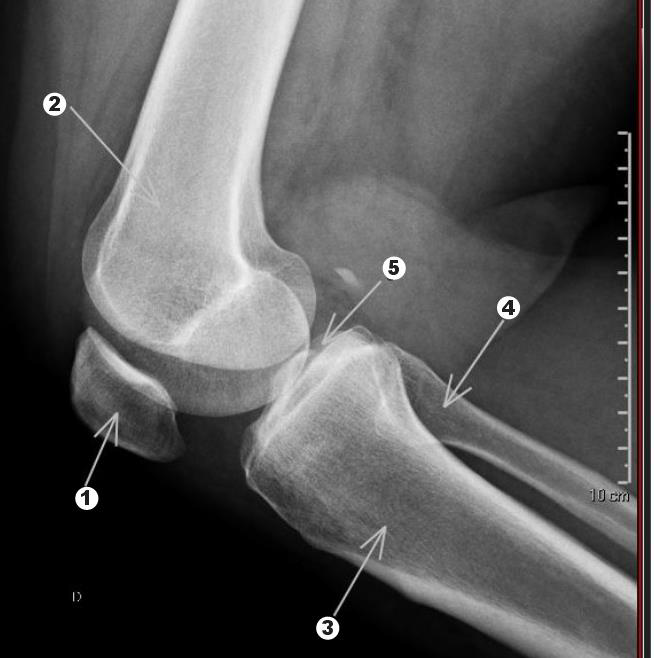

Observe a figura a seguir.

Identifique as estruturas assinaladas por números e setas.

A sequência correta, de 1 a 5, é: